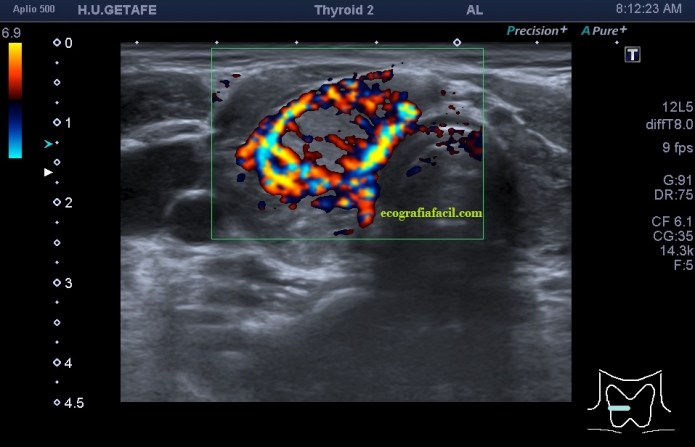

De la imagen 1 a 7 el protocolo habitual, el estudio particular del nódulo con medidas y aplicación del doppler demuestra el aspecto típico del Caballero Blanco.

De la 8 a la 11 estudio con Doppler.

- Doppler Color y Doppler Power aumentado de tamaño en el nódulo